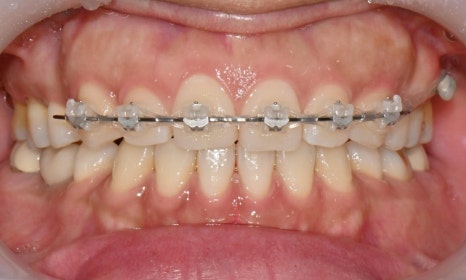

2025.3.5 초진

본 환자는 예전에 발치교정을 했는데 과개교합 때문에 위 치아 유지장치 관리가 잘 되지 않아 앞니가 살짝 벌어지고 치아 하나가 튀어나온 것이 신경이 쓰인다는 주소로 병원에 내원하셨습니다. 과개교합 때문에 위아래 앞니가 서로 부딪혀서 유지장치가 떨어졌고, 유지장치 관리가 잘 안되니 앞니 사이가 점점 벌어지고 오른쪽 앞니가 튀어나온다고 하셨습니다.

장치 교정을 할 경우 사회생활을 하는데 비심미적이고, 기간이 오래 걸려서 빠른 시일 안에 교정 치료를 원하셔서 위 앞니만 인비절라인 익스프레스로 진행하길 원하셨습니다.